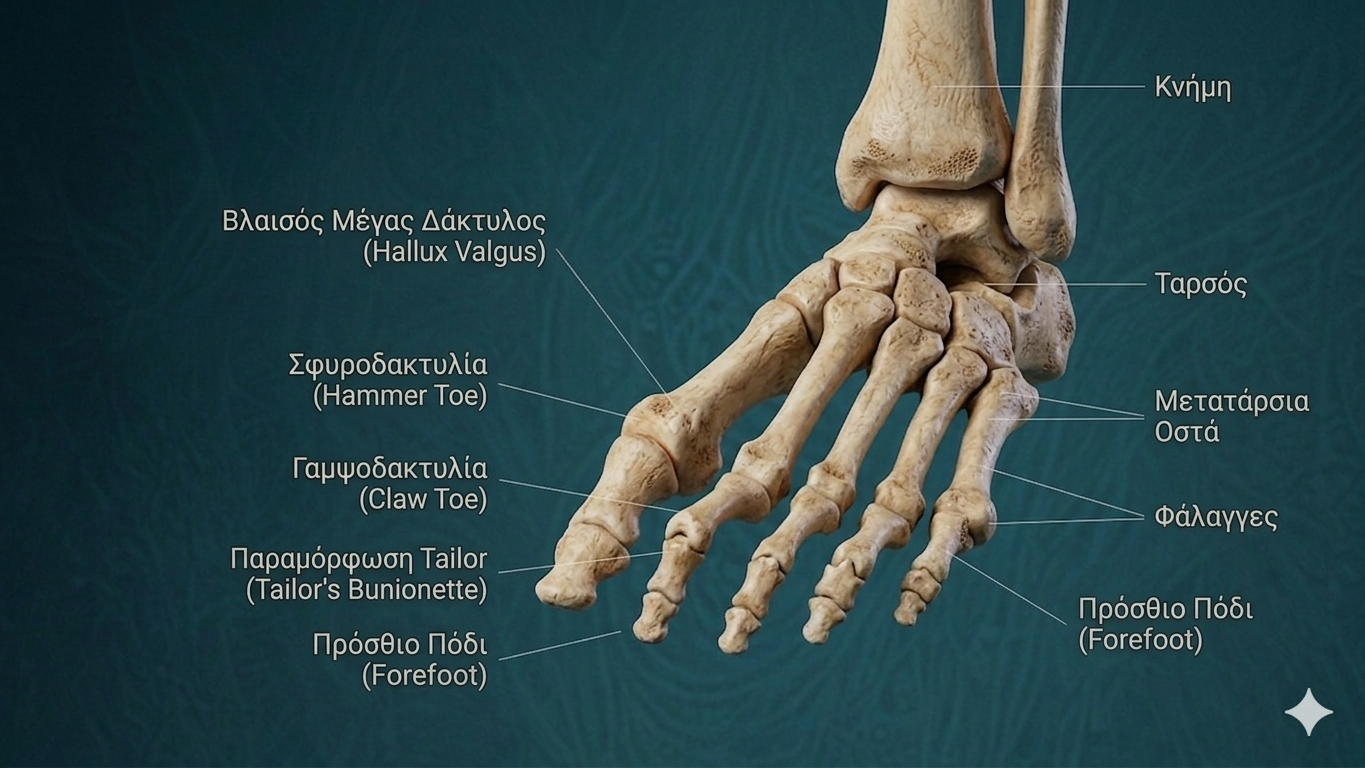

Η εφίππευση δακτύλου (crossover toe) είναι μια προοδευτική παθολογία κατά την οποία ένας δάκτυλος του ποδιού — συνήθως ο δεύτερος — σταδιακά μετατοπίζεται από τη φυσιολογική θέση του και τελικά «περνάει» πάνω ή κάτω από τον γειτονικό δάκτυλο. Η πάθηση αφορά κυρίως τη δεύτερη μεταταρσοφαλαγγική (MTP) άρθρωση και σχετίζεται άμεσα με τη βλάβη της πελματικής πλάκας (plantar plate).

Η εφίππευση του δεύτερου δακτύλου συνυπάρχει πολύ συχνά με το κότσι. Καθώς ο μεγάλος δάκτυλος αποκλίνει προς τον δεύτερο, δημιουργείται μηχανική πίεση που εκτοπίζει τον δεύτερο ραχιαία και έσω. Η αντιμετώπιση και των δύο παθήσεων ταυτόχρονα είναι συχνά απαραίτητη για ένα βιώσιμο αποτέλεσμα.